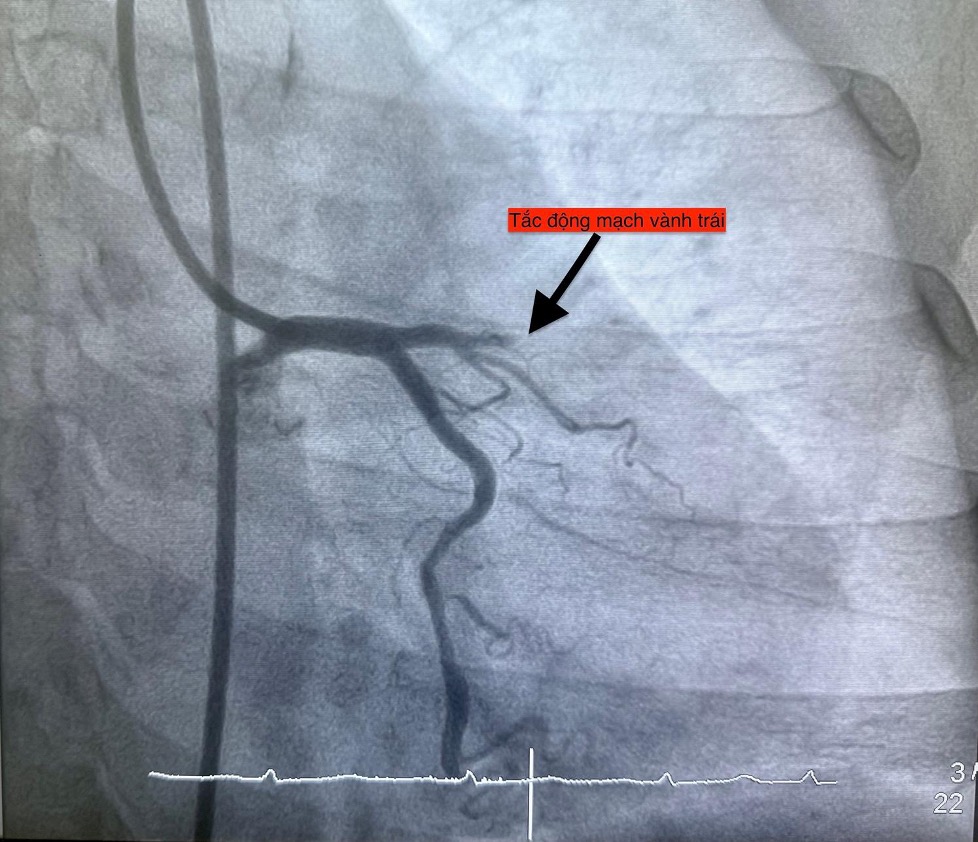

Trường hợp thứ tư, lúc 22 giờ 6 phút, nữ bệnh nhân 61 tuổi nhập viện vì đau ngực, vã mồ hôi; bệnh nhân có đái tháo đường type 2. Điện tim cho thấy nhồi máu cơ tim cấp thành trước.

Hình ảnh chụp mạch vành cho thấy các bệnh nhân bị tắc mạch máu tim (do mảng xơ vữa, huyết khối) dẫn đến tình trạng thiếu máu cục bộ và nhồi máu cơ tim cấp